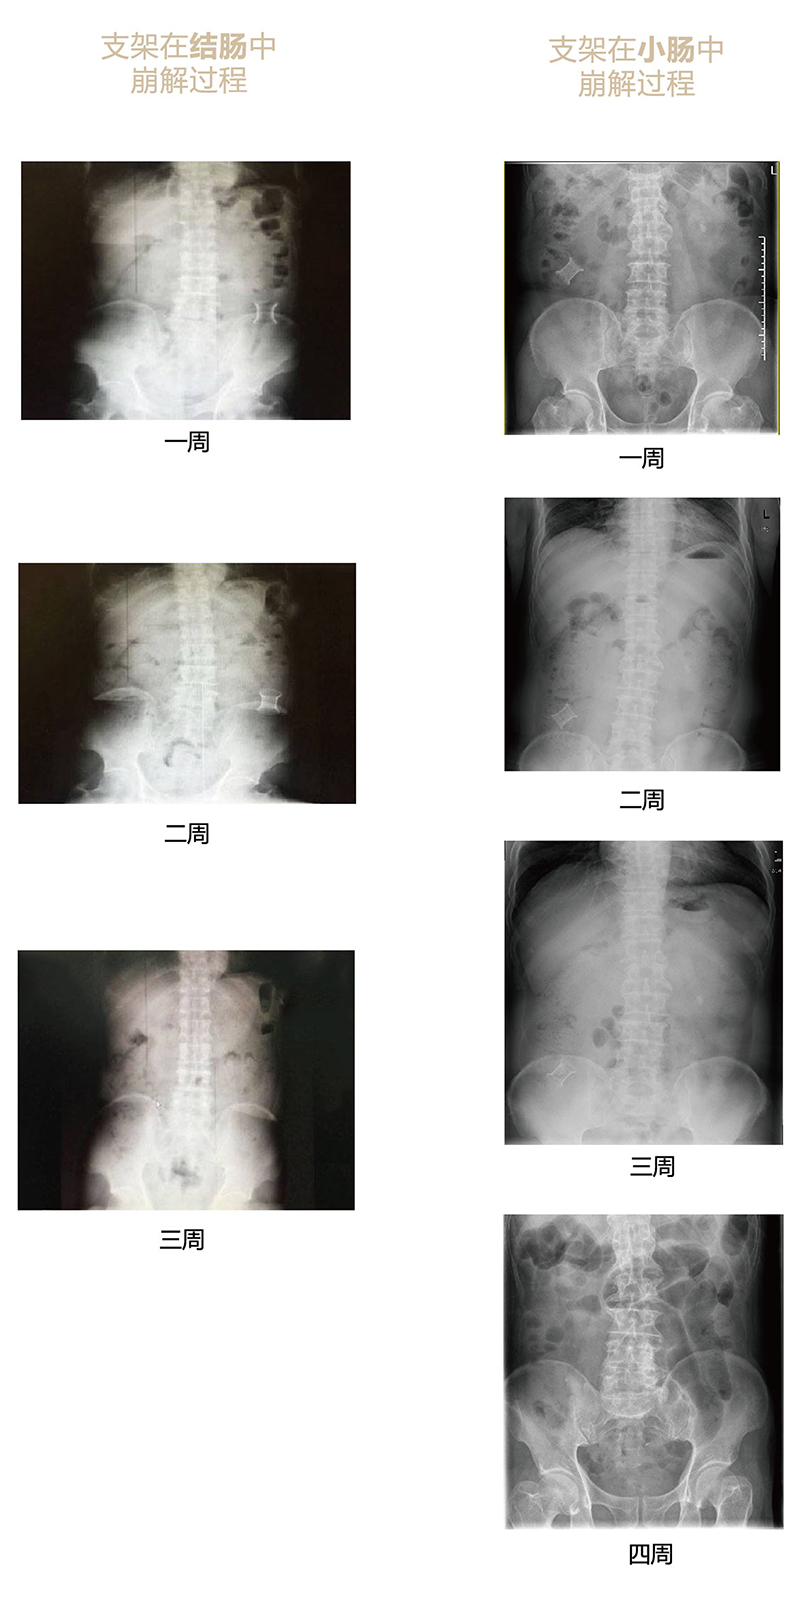

“可崩解腸道吻合器”由聚乙醇酸(PGA)與硫酸鋇按重量比7:1混合注塑制成,在X線下顯影,可動(dòng)態(tài)追蹤可崩解腸道吻合器(支架)在腸道內(nèi)崩解過(guò)程。

為解決該問(wèn)題,蔡秀軍教授在“支架法空腔臟器吻合技術(shù)”的理念基礎(chǔ)上,又發(fā)明了“蔡氏腸轉(zhuǎn)流術(shù)”,這是一種應(yīng)用“可崩解腸道吻合器HB型(可崩解腸轉(zhuǎn)流支架)”(發(fā)明專利號(hào):201910794214.3),的支架法腸道轉(zhuǎn)流術(shù),此創(chuàng)新術(shù)式既能保護(hù)低位吻合口,更避免了回納術(shù)??杀澜饽c轉(zhuǎn)流支架在直腸癌根治術(shù)中植入遠(yuǎn)端回腸,可確保完全阻斷腸腔,用腸造瘺管在轉(zhuǎn)流支架近端行腸造瘺,起到完全轉(zhuǎn)流的作用。腸轉(zhuǎn)流支架在二至三周內(nèi)逐漸崩解,并在四周內(nèi)完全排出體外,恢復(fù)腸道通暢后拔除造瘺管,避免了傳統(tǒng)造口回納的二次手術(shù)。該創(chuàng)新術(shù)式具有方法簡(jiǎn)單、吻合時(shí)間短、人體內(nèi)無(wú)異物永久殘留、不破壞吻合口粘膜下血管,并能預(yù)防吻合口漏、可避免人工肛門(mén)留置及二次手術(shù)、治療周期可縮短至二至四周、患者生理心理創(chuàng)傷顯著減少。